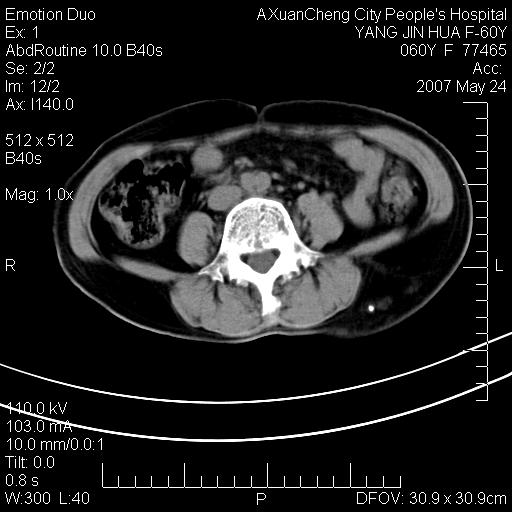

发现左侧腰背部包块40余年,逐渐长大,质软,局部表面可见扩张的血管影

左背部皮下良性肿瘤,密度不均,边界不清,内有脂肪、钙化,增强扫描无明显强化,血管平滑肌脂肪瘤?进一步诊断有困难,建议穿刺活检。

左侧背部皮下混杂密度肿块,结构较疏松,边缘欠光整,内有多发斑点状钙化,考虑:皮下血管瘤。